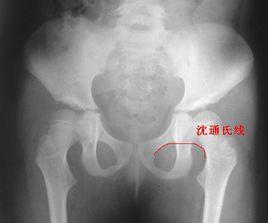

沈通氏線 (Shenton‘s 線):是指正常骨盆X線中恥骨下緣弧形線與股骨頸內側弧形線連成的弧度。

1、沈通氏線連續,說明關節位置目前位置良好。

2、沈通氏線不連續,關節脫位或者半脫位。